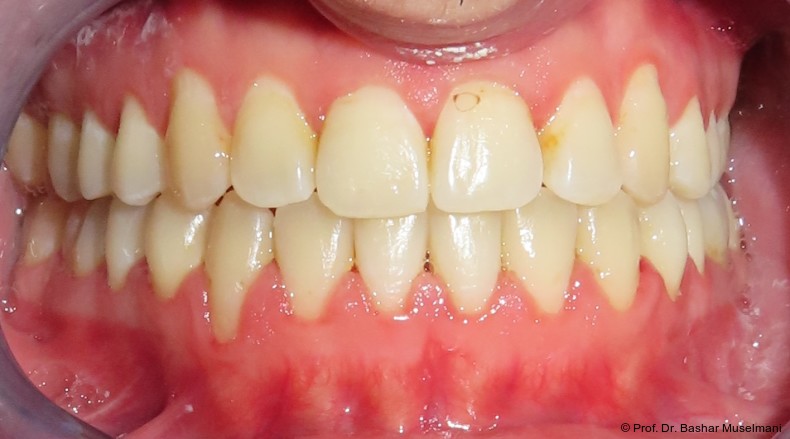

Der Patient (28 Jahre 8 Monate) stellte sich mit einer skelettalen Klasse III sowie einer Mittellinienabweichung nach links vor.

Klinische Befunde

• leicht konkaves Gesichts- und Mundprofil

• posterior positionierter Unterkiefer (VW)

• retroinkliniert stehende Unterkieferfront

Die Abbildungen 1 bis 3 zeigen die initiale klinische und radiologische Ausgangssituation.